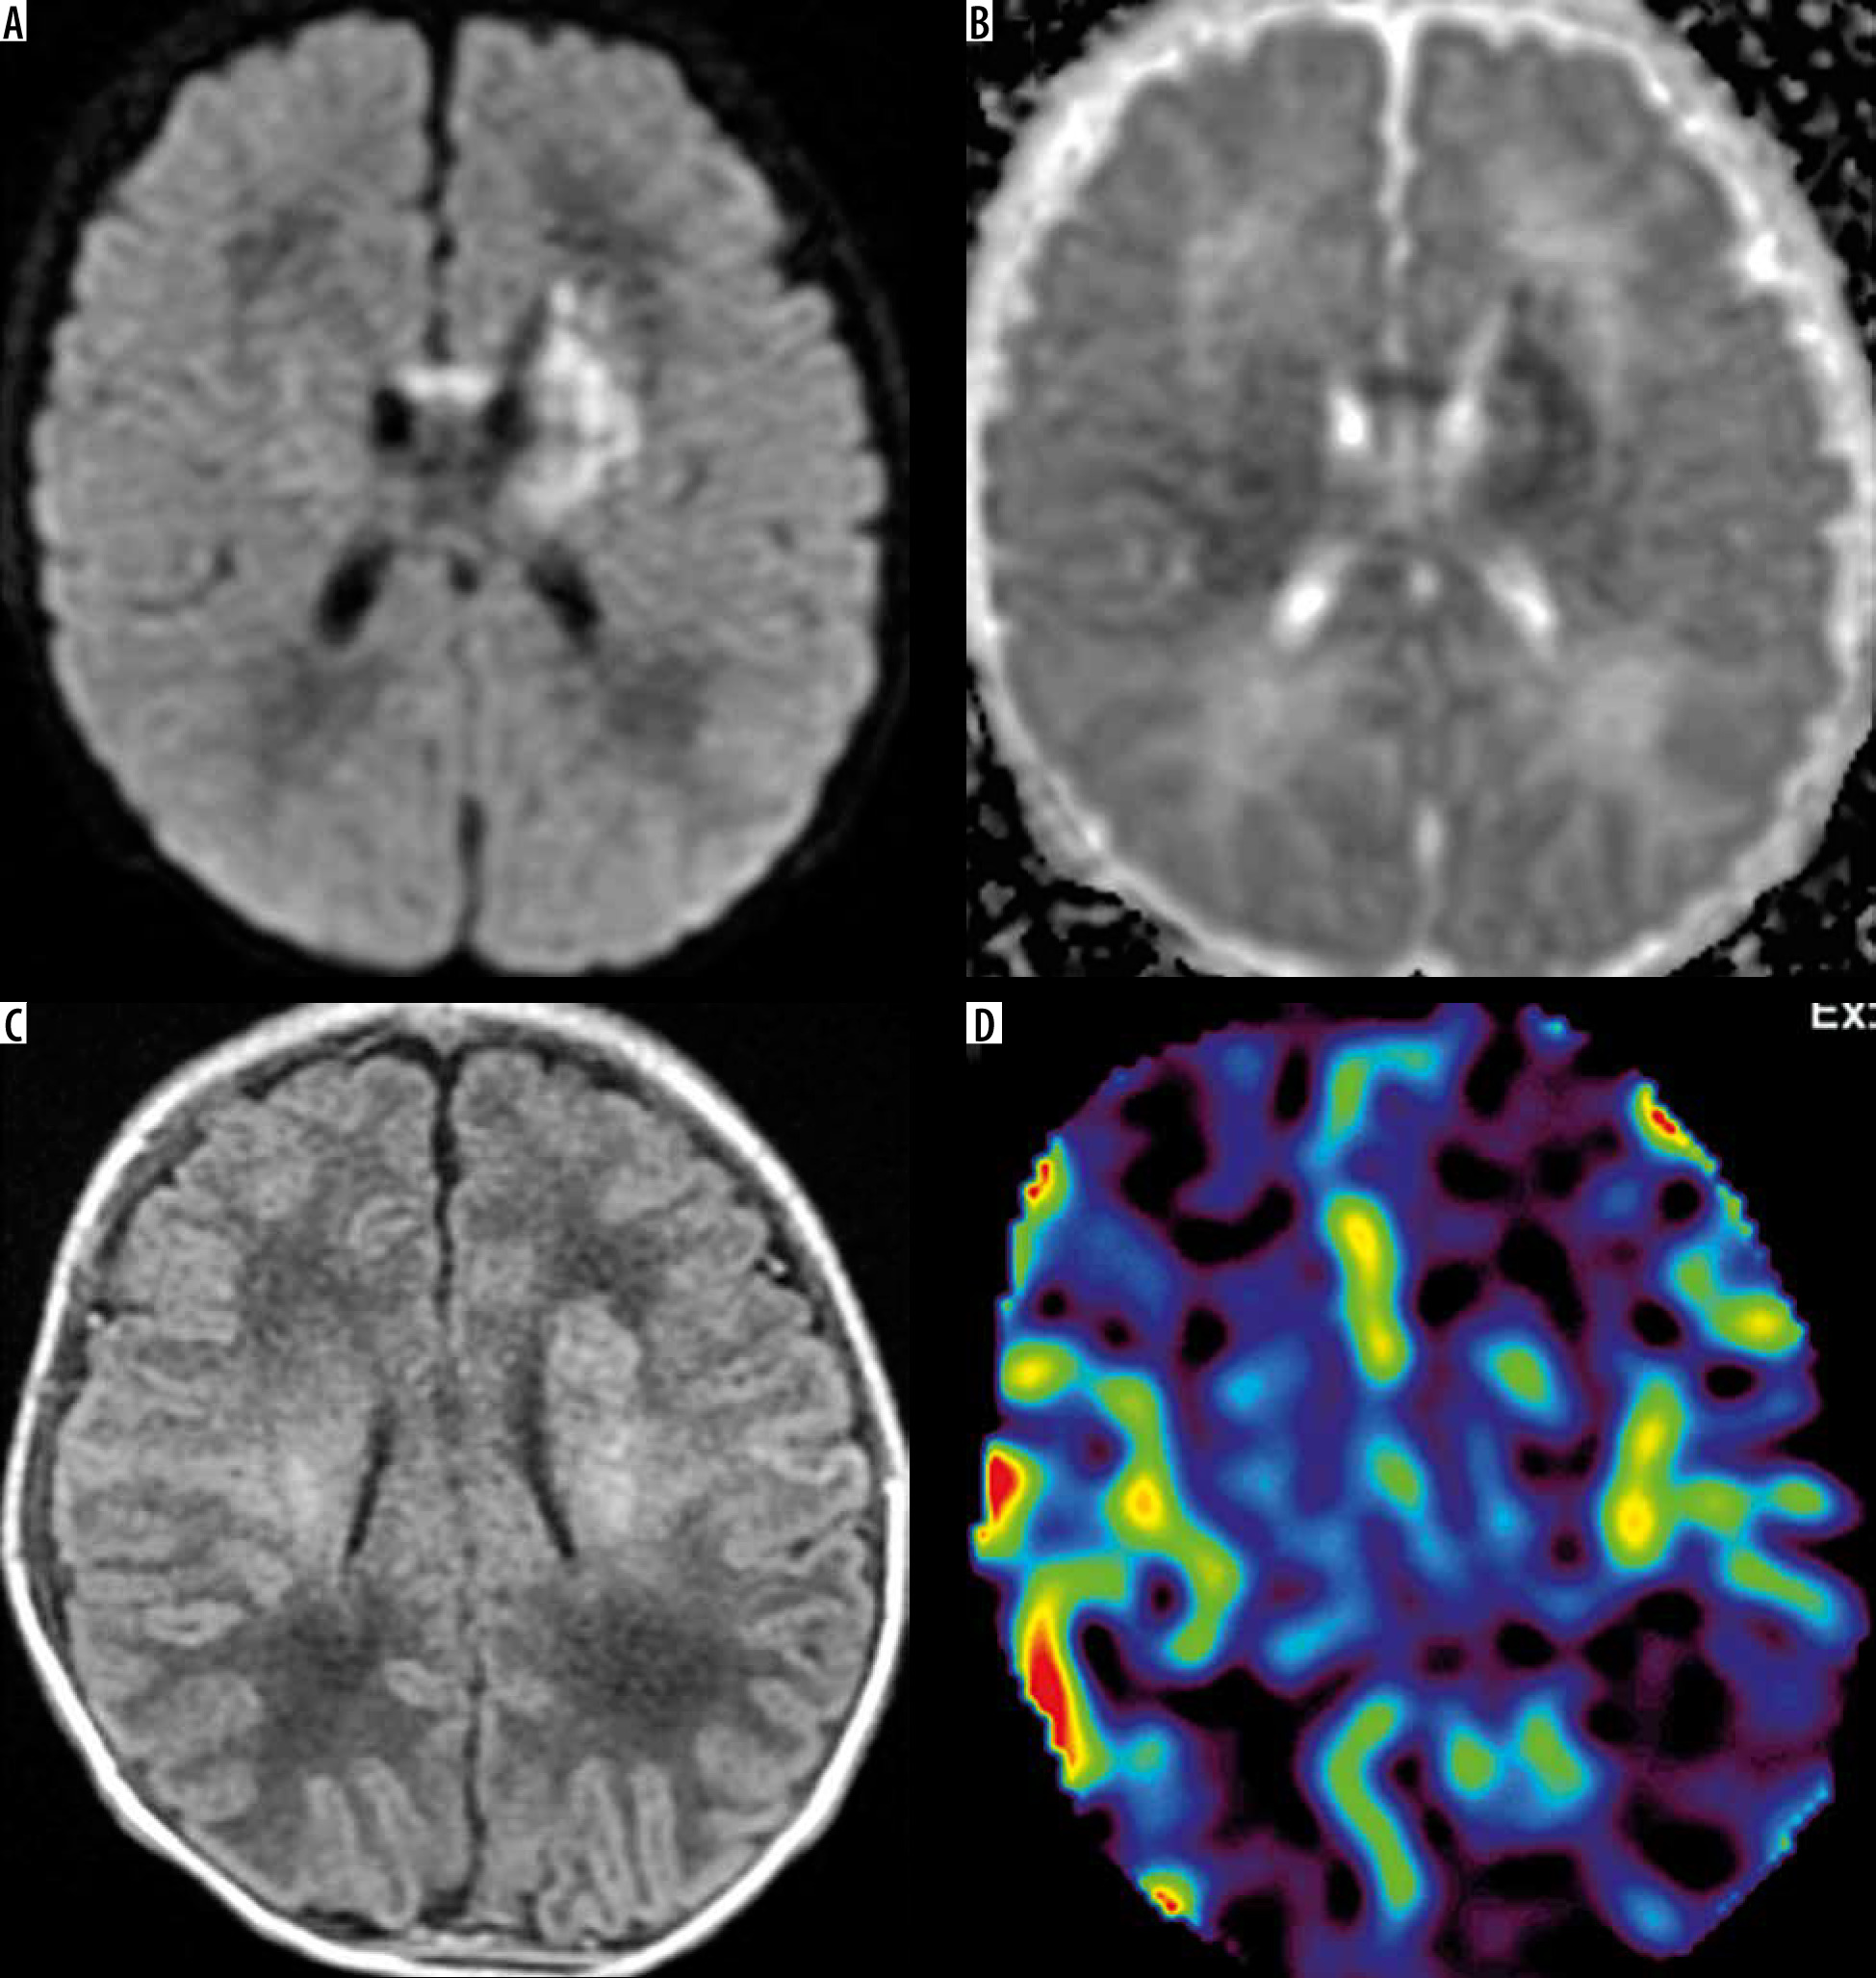

Neonatal stroke has already been described in ASL in a few cases [7]. Our findings are similar to those already reported: hypoperfusion in the area of stroke (pt. no. 5) (Figure 5) or hypoperfusion with peripheral hyperperfusion (pt. no. 6). Obviously, in these cases DWI with ADC map was the main diagnostic sequence.

Figure 5

Patient no. 5 after perinatal ischaemic stroke in the area of left middle cerebral artery (DWI – A, corresponding ADC map – B, T1flair – C) with decreased perfusion in the area of stroke on CBF map (D)